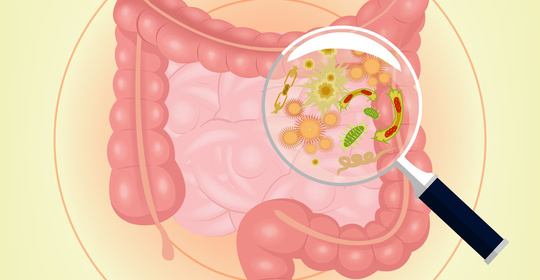

新生兒拉肚子:原因與處理方法

新生兒拉肚子:舒腹達(Diosmectite)治療與護理要點

本文介紹了新生兒拉水便時的處理方法。首先建議家長在醫生指導下使用舒腹達(Diosmectite)進行治療,並密切觀察寶寶的症狀變化。同時,應保持寶寶良好的飲食習慣,避免食用過於刺激性的食物。此外,家長還要注意觀察寶寶的精神狀態及尿量,確保其水分攝入充足。

新生兒拉肚子:常見問題及處理

新生兒拉肚子:處理方法與注意事項

新生兒拉肚子:就醫、腹部按摩、飲食調整、藥物使用